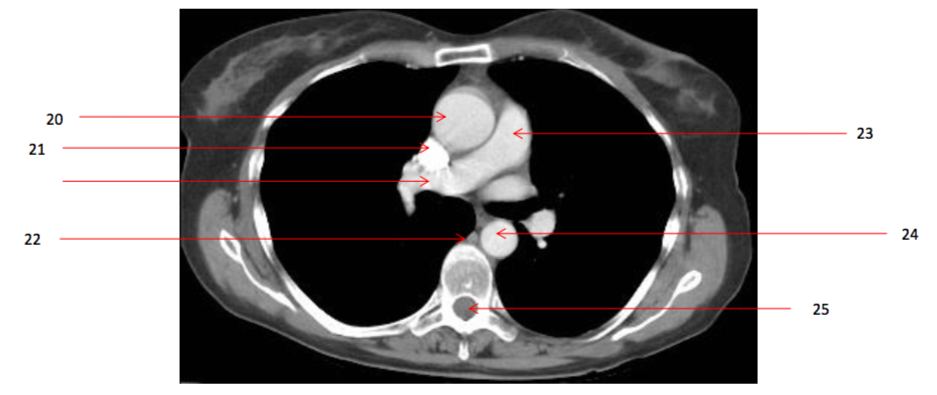

Number 17?

Number 18?

Number 21?

Number 22?